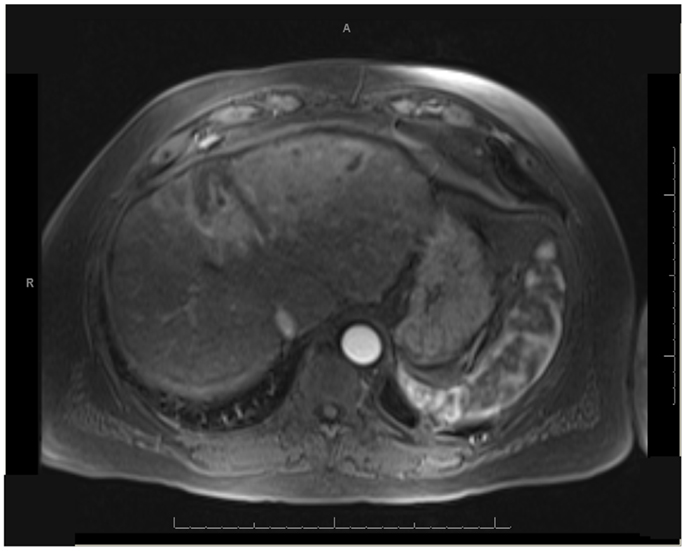

One patient was able to receive a left hepatectomy following RE and sorafenib. This patient was a 60-year-old male with cirrhosis who was diagnosed with HCC in segment IV. He did not meet Milan criteria for liver transplantation due to the 6.7 cm size of the tumor and questionable vascular invasion (Figure 7). He also had non-specific mediastinal lymph node enlargement and a 3 mm right lung nodule at presentation that were suspicious for metastatic disease. He had a left portal vein thrombosis, making him ineligible for TACE. He was Child-Pugh class A, BCLC stage C. He was started on sorafenib at 400 mg BID, and RE with resin Y-90 microspheres was delivered through the left hepatic artery 10 days later. The activity administered was 48.5 mCi, giving a calculated dose of 44.5 Gy to the liver lesion. He experienced mild short-term fatigue, anorexia, and diarrhea following RE. Follow-up imaging from 7 weeks post-RE and 15 weeks post-RE showed significant tumor response (Figures 8 and 9), with well-preserved liver function. He also had an 83% decrease in his serum AFP from 5675 to 957 ng/mL following RE. His sorafenib was stopped 2 weeks prior to the extended left hepatectomy (Figure 10) that the patient received 18 weeks after RE.

FIGURE 7

www.frontiersin.org

Figure 7. T1 MRI with early phase contrast. Pre-radioembolization.